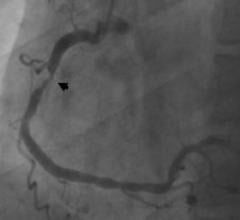

Coronary angiography is unable to accurately predict the severity of vessel narrowing, suggesting fractional flow reserve (FFR) functional tests should be added to help determine if a patient needs revascularization. This was according to research presented from the IRIS FFR-DEFER trial at the American College of Cardiology's (ACC) 61st Annual Scientific Session this week in Chicago.